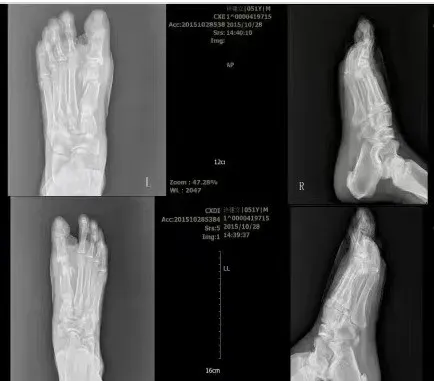

术后通过便携式射线机查看截骨情况

上图为术前术后对比图

术前术后X光片对比图